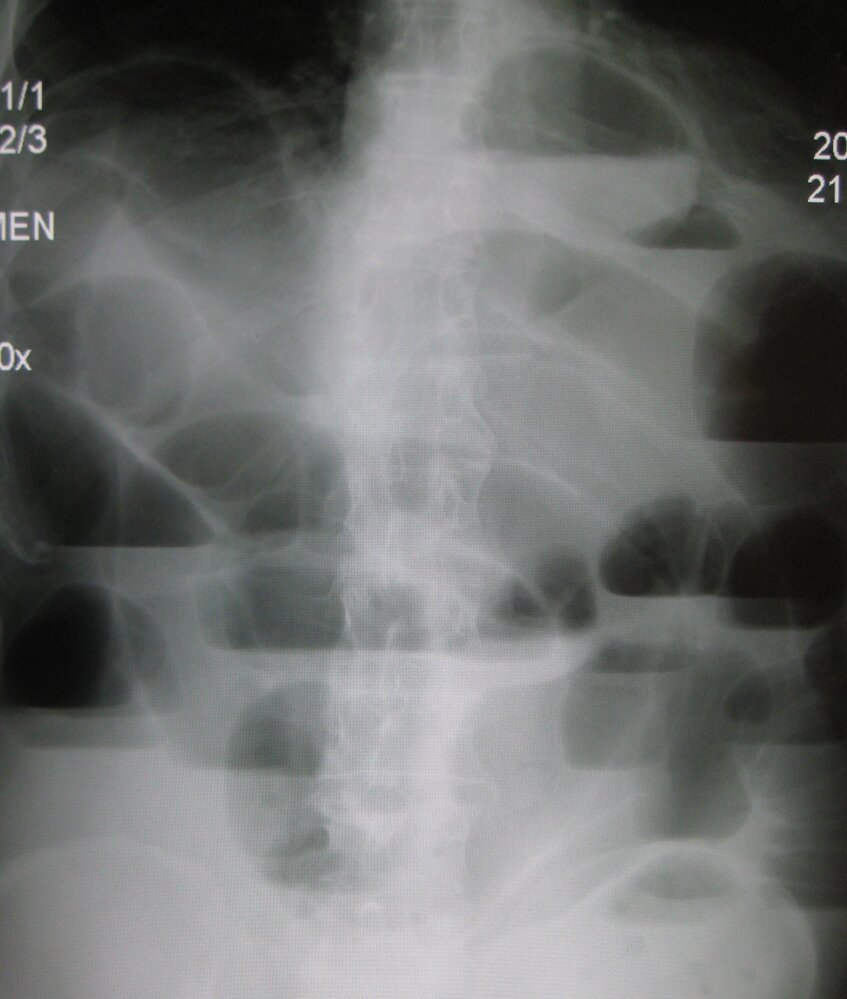

• Abdominal x-ray: may be used to rapidly evaluate for bowel obstruction and perforation

Findings

• Direct visualization and quantification of the fascial defect(s)

• Presence of viscera in the hernial sac

• Strangulated hernia: signs of visceral ischemia [25]

• Obstructed hernia: radiological signs of mechanical bowel obstruction